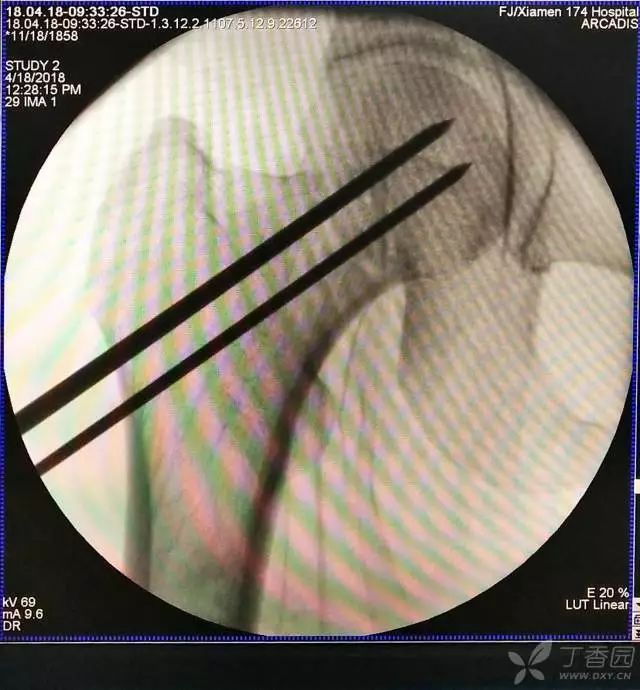

4. 先体外放置一枚导针导引进针方向

5. 打入第一枚倒品字下方导针,跟体外导针基本重叠

6. 然后依次打入倒品字上方的两枚导针